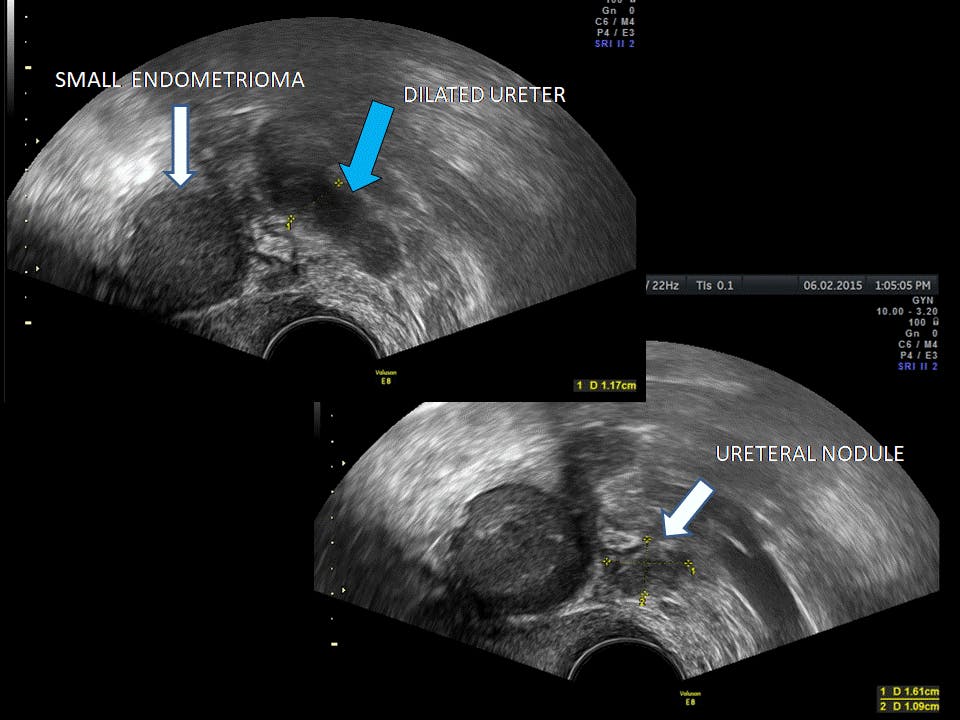

A kidney and bladder ultrasound, or renal ultrasound, uses high frequency sound waves transmitted through a transducer (probe) to visualize and assess your kidneys, ureters (small muscular tubes that join the kidneys with the bladder) and urinary bladder. About 36% of these are medical ultrasound instruments. The removal of kidney stones involves ultrasound treatment to break up. When you urinate, urine passes from your your urinary system — which includes the kidneys, ureters, bladder and urethra — is responsible for removing waste from your.